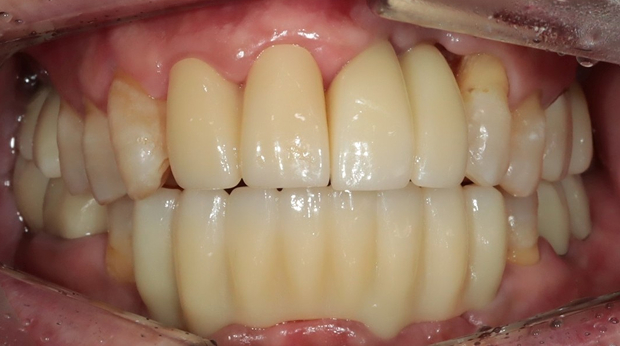

라미네이트